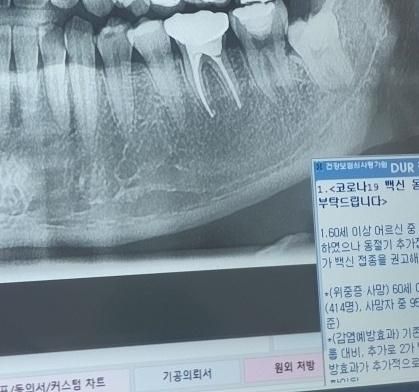

사랑니를 뽑고 싶은데 사랑니 뿌리가 깊게박혀있고 신경에 말려있다는데 뽑을시 신경 손상이 얼마나 될까요ㅠㅠ?

영구마비 올 정도 일까요?

사진으로만 봤을 경우에는 사랑니의 뿌리가 신경과 인접해 있는 것으로 보입니다. 완전히 매복되어 있으며 문제를 발생시키지 않는 사랑니의 경우에는 발치를 하지 않아도 큰 문제가 문제가 되지 않기 때문에 굳이 발치를 하지 않아도 될 것으로 생각됩니다. 자세한 확인을 위해서 치과에서 진료를 받아보는 것을 권유드립니다.

정확한건 CT를 찍어봐야 알겟지만 그렇게 난이도가 높진않으면 신경손상도 크게 걱정은 안하셔도 될것같습니다.

신경손상은 가능성의 부분입니다 엑스레이상 저렇게 보여도 신경을 사랑니가 관통하고 있는게 아니므로 뽑으면서 무조건 신경에 손상을 유발하는건 아니지만 이제 사랑니를 뽑다보면 치아 움직임을 유발하고, 기구 조작 등에 의해 신경마비 유발 가능성이 있습니다